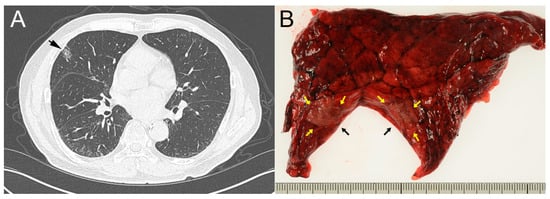

2. Case Report